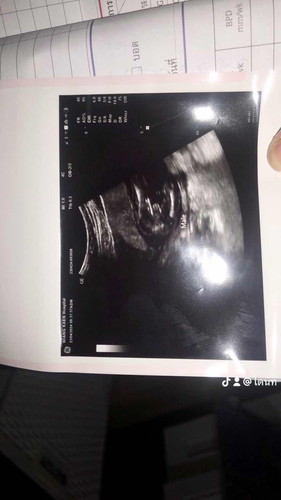

ดีใจและตื่นเต้นมาก19+4 น้องเป็นผู้ชายค่ะ

แม่ลุ้นแทบตื่นเต้นคุณหมอบอกผู้ชายคับ น้องแข็งแรงปกติดี ถ่านขาไม่อายคุณหมอเลยนะ อีแม่ยิ้มหน้าบาน สมใจพ่อเขาลูกชายคนแรกค่ะ

จู๋ชัดมากค่ะแม่

น้องค่อนข้างเป็นคนเปิดเผยค่ะแม่🤣